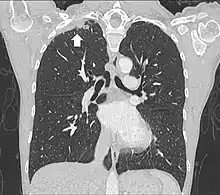

Tomodensitométrie

Le scanner thoracique permet d'analyser avec précision la localisation de la tumeur, de mesurer sa taille, et de rechercher des adénopathies médiastinales[11]. Idéalement, il doit être injecté d'un produit de contraste iodé afin de préciser les rapports vasculaires[11].

L'IRM thoracique permet d'analyser l'envahissement du plexus brachial et de la paroi thoracique osseuse, ainsi que du rachis avec plus de précision que la tomodensitométrie[11]. L'envahissement des trous de conjugaison à l'IRM est ainsi une contre-indication chirurgicale. Pour cette raison, il est recommandé de réaliser une IRM dans le cadre du bilan préopératoire.